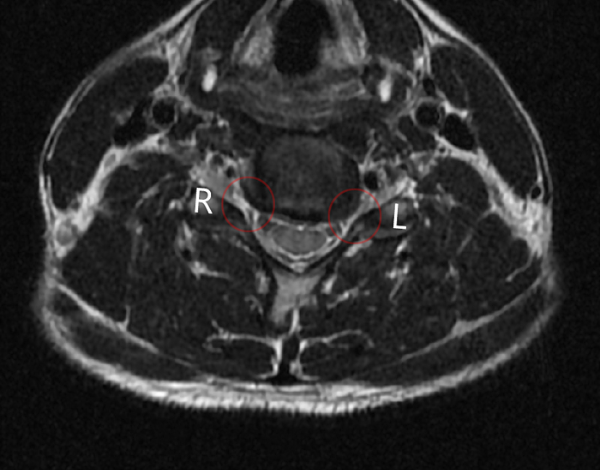

MRI는 단면 사진도 볼 수 있는데요.

L이라고 표시한 게 왼쪽입니다.

저기가 신경이 지나는 부분인데 확실히 오른쪽에 비해서 좁아진 게 확인되더라고요.

디스크가 나와서 신경을 눌러서 통증도 있고 저림 증상이 있는 게 이런 이유라니 참 신기하더라고요.

유독 왼쪽만 아픈 것도 왜 그런지 알 수 있었습니다.